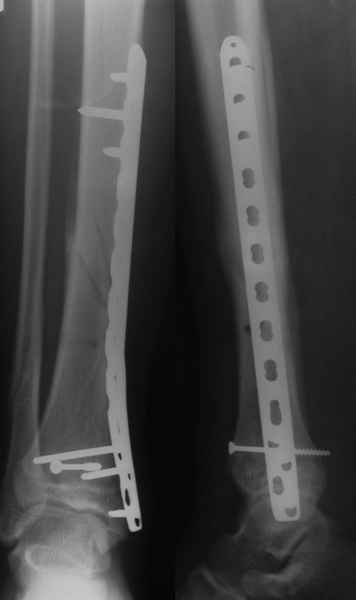

Уважаемый Иван! Если есть ЭОП, то перелом подходит для малоинвазивной

фиксации. Репозиция суставного отдела (использовать репозиционные

щипцы)и его фиксация стягивающими винтами чрезкожно, затем пластина

медиально малоинвазивно, лучше метафизарная. Если не располагаете

подходящим имплантом или непозволяют мягкие ткани, вполне возможно

применить вместо платы Fix.Ex. В приложении метафизарный перелом у

ребёнка 14лет, с распространением линии перелома на зону роста.